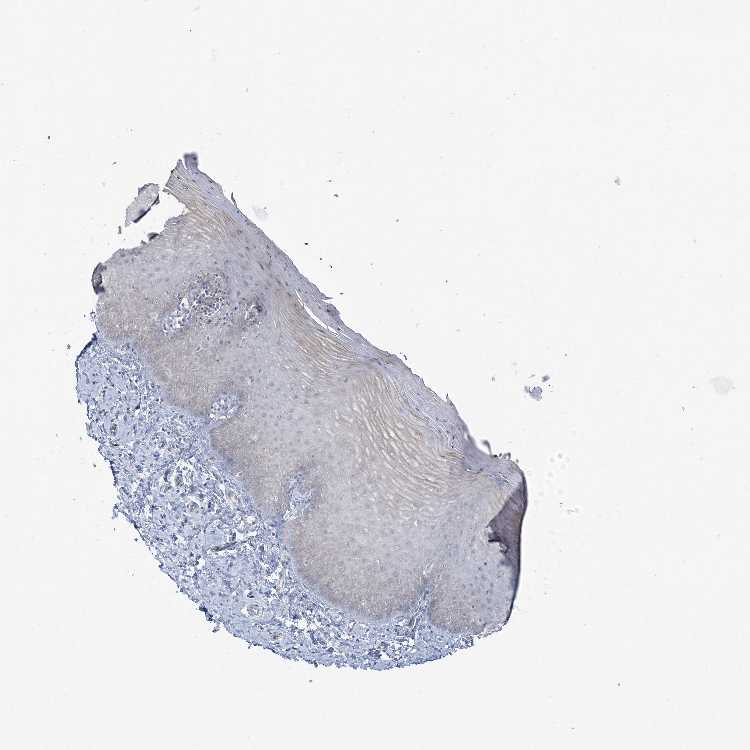

CERVIX - Antibody stainingi

Antibody staining in the annotated cell types in the current human tissue is reported as not detected, low, medium, or high, based on conventional immunohistochemistry profiling in selected tissues. This score is based on the combination of the staining intensity and fraction of stained cells.

Each image is clickable and will lead to virtual microscopy that enables deeper exploration of all samples and also displays staining intensity scores, fraction scores and subcellular localization as well as patient and tissue information for each sample.

Antibody HPA036531

Glandular cells Not detected

Squamous epithelial cells Not detected

Information about each individual sample is listed below, including gender, age, a tissue section image and estimated fractions of cell types. nTPM (normalized transcripts per million) values give a quantification of the gene abundance which is comparable between different genes and samples.